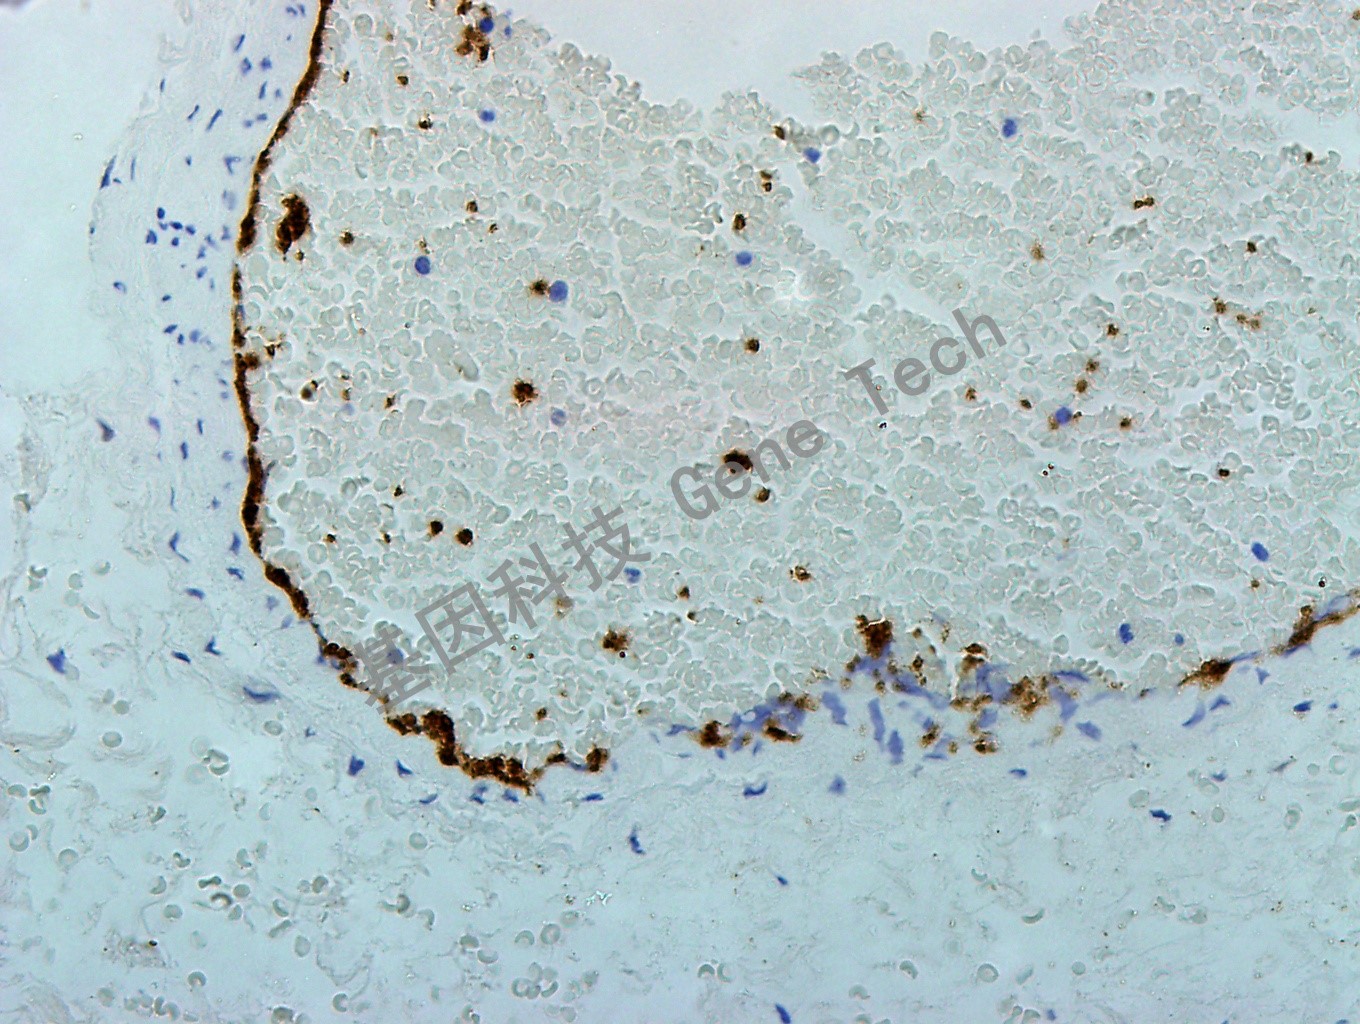

| 预处理:高pH热修复 | 阳性部位:细胞膜 | 阳性对照:扁桃体 |

| 扁桃体石蜡切片,用 CD42b(GT2238)染色,细胞膜阳性,DAB 显色。 | ||